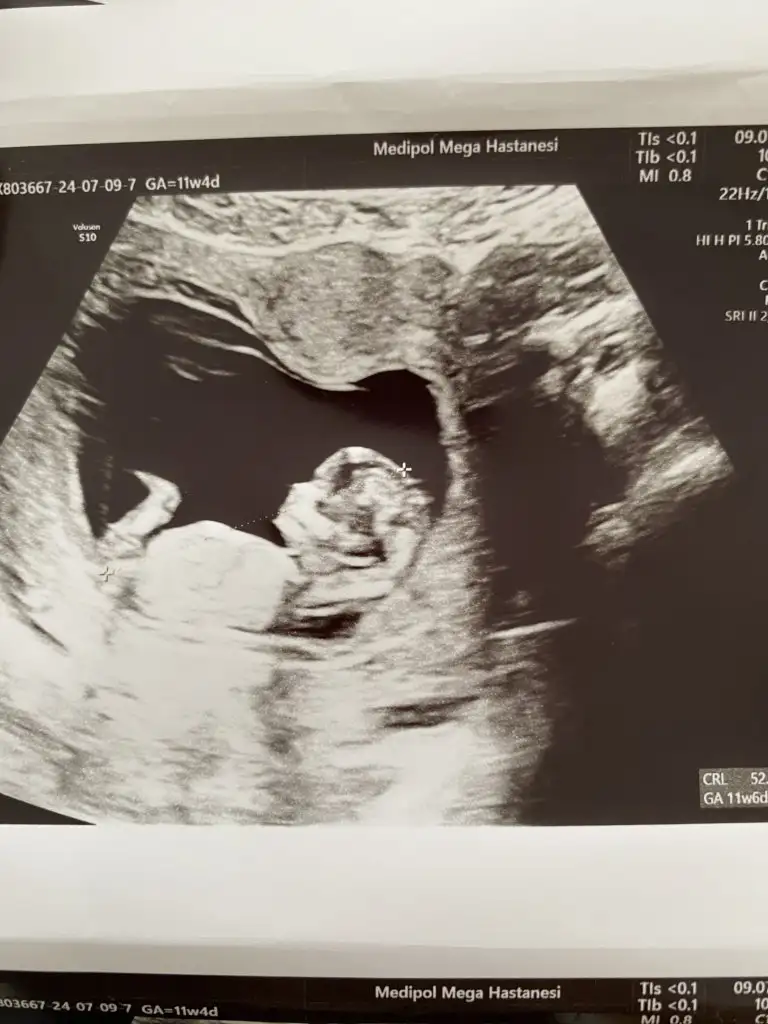

Ben de dün kontrole gittim 11+4te. Uyuyordu benimki de, doktor biraz rahatsız edelim dedi ama yok uyandırmadıkKuzum doktor öyle dedi zaten gittim meyve suyu içtim bişeyler yedim çok su içtim gittim uyanmadı bazı bebekler böyle olur dedi 22. Haftaya kadar hem göstermez hem hareketsiz olur dedi bakalım senin nasıl geçecek

Ayy bacak arası 3cizgi mi var bana mı öyle geliyor.genelde takip ettiğim Dr lar 3cizgide kız diyorlar.Bu arada doktor cinsiyet için daha erken ama şimdilik bacak arasında bir çıkıntı vs görünmüyor dedi. Sizler ne dersiniz kızlar